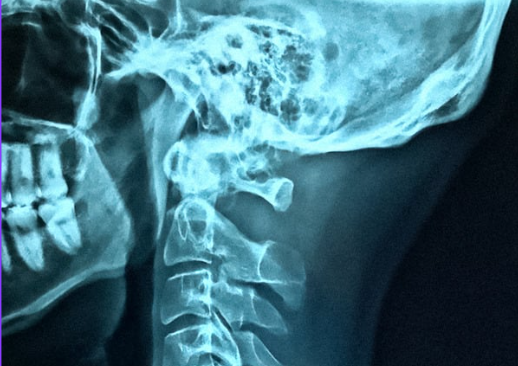

Prześwietlenie czaszki - Getty images

Fot. Getty images